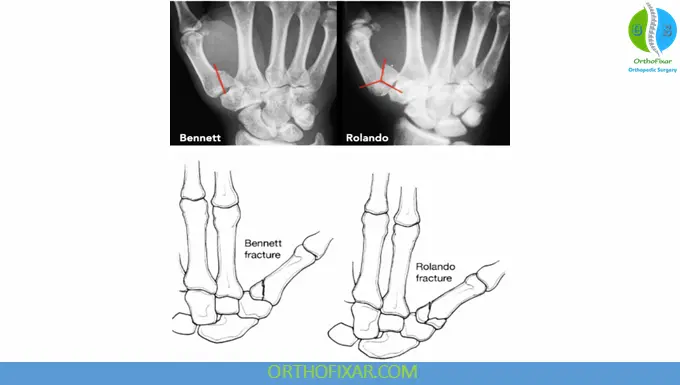

A Rolando fracture is a comminuted intra-articular fracture at the base of the first metacarpal (thumb). It typically presents with a “Y-shaped” or “T-shaped” fracture pattern, involving multiple fragments and extending into the carpometacarpal (CMC) joint.

This injury was first described in 1910 by the Italian surgeon Silvio Rolando and is considered a more severe variant of thumb base fractures compared to Bennett fractures.

Although no universally accepted classification exists, Rolando fractures are generally:

- Classic type: Y- or T-shaped (3 fragments)

- Comminuted type: multiple fragments (more severe)

Rolando vs Bennett Fracture

| Feature | Rolando Fracture | Bennett Fracture |

|---|---|---|

| Pattern | Comminuted (≥3 fragments) | Two-part fracture |

| Stability | Highly unstable | Less unstable |

| Prognosis | Worse | Better |

| Treatment | Usually surgical | Sometimes conservative |